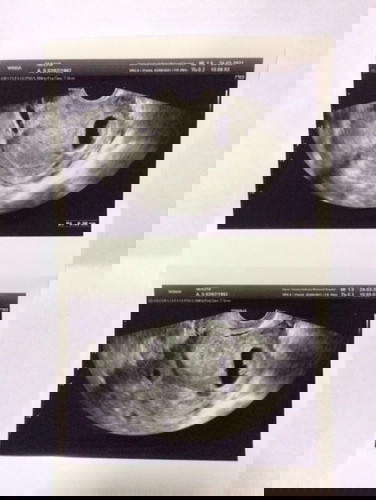

แม่ๆท่านไหนเคยเจอเคส แบบนี้บ้างคะ น้องฝังตัวทางด้านซ้ายของมดลูก มีผลข้างเคียง หรืออันตราย แบบไหนบ้าง ตอนนี้แม่กลุ่มมากๆเลย คะ ไปหาหมอ มีแต่ติดตามอาการว่า ปวดท้องน้อย หรือเปล่า มีเลือดออกทางช่องคลอดไหม แต่ไม่สามารถบอกเราได้เลยว่า อันตรายมากน้อยแค่ไหน แม่ๆท่านไหนเคยเจอหรือรู้ จักเคสแบบนี้ช่วยบอกทีค่ะ ตอนนี้น้องได้ 12+ แล้วคะ#ขอบคุณล่วงหน้านะคะ